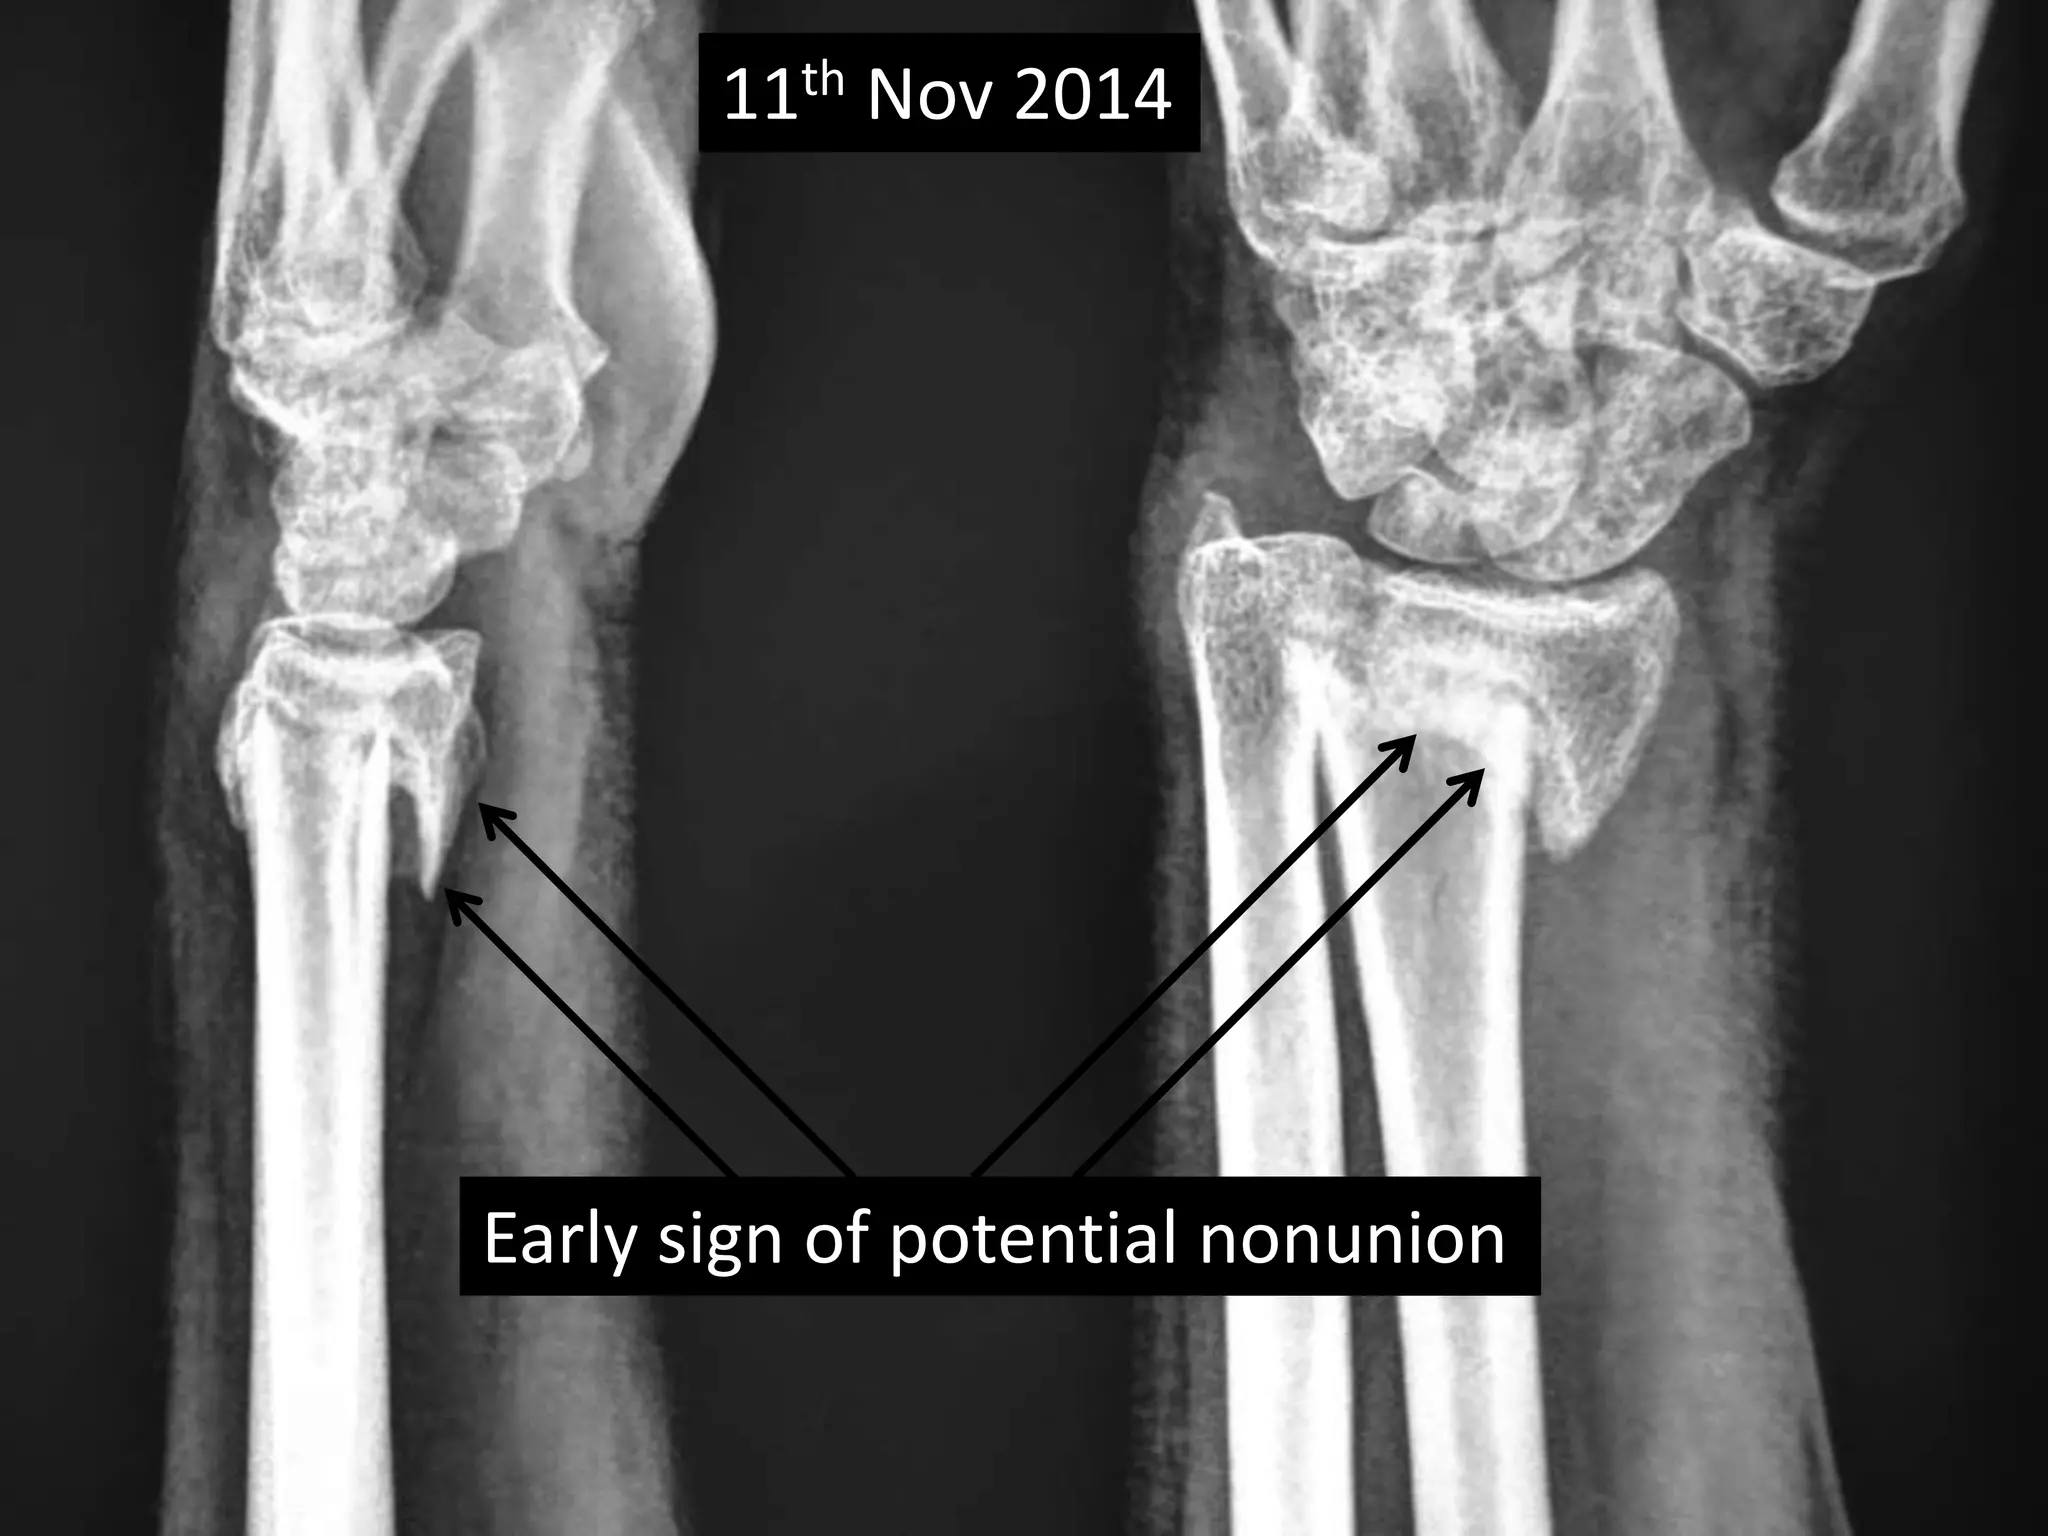

Case three •40 years old Female, • Sustained fracture lower end radius on 13th Sept 2014. • Received no treatment. • No co-morbidity. • Chief complaint was deformity of wrist. • X-rays on 11th Nov 2014 showing delayed union • Clinically no disability. • Patient refused corrective surgery.

11th Nov 2014 Early sign of potential nonunion